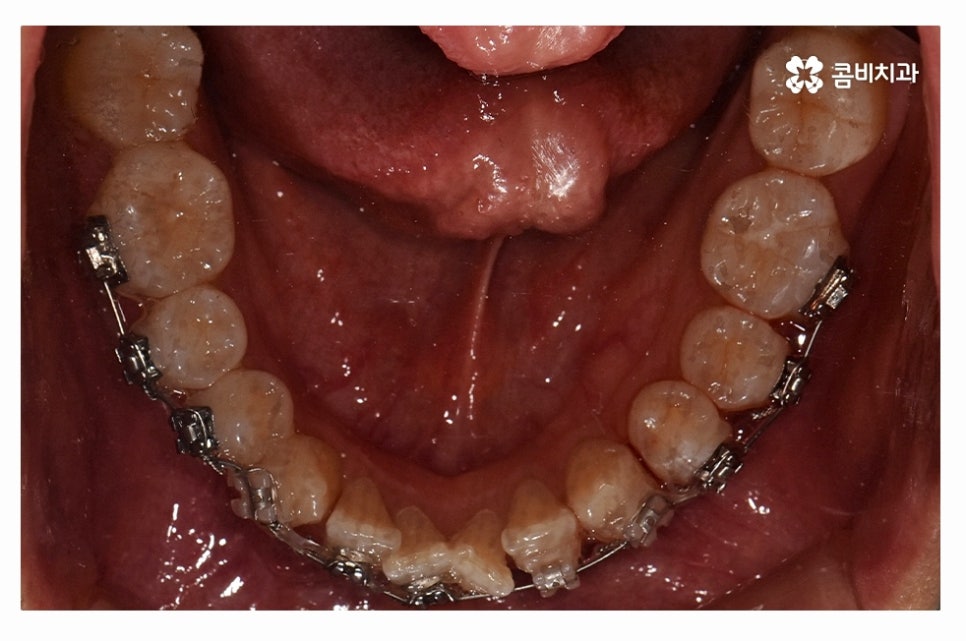

오늘 보여드릴 사례도 덧니교정이 비발치로 진행이 된 사례이며

치아의 이동 공간과 치아 상태, 골격, 얼굴형 등을

종합적으로 판단할 때 비발치로도 진행이 가능했던 사례라고 할 수 있어요.

위 환자분의 사례처럼 클리피씨교정이 보편적으로 많이 활용되고 있는데요.

클리피씨교정은 치아의 이동이 일반 장치에 비해 상대적으로

빠르기 때문에 치료 기간이 단축될 수 있으며

통증의 감소, 내원 횟수를 줄일 수 있다는 장점 등이 있어요.